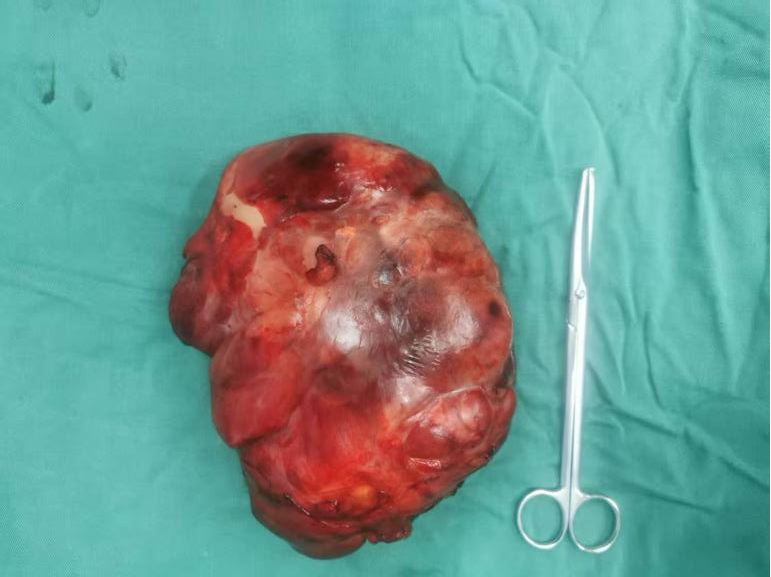

手術由胃腸(肛腸、疝)外科汪勇副主任醫師和肝膽胰外科周寶勇副主任醫師共同主刀,成功地將這個巨大的腫瘤完整切除。目前,楊阿姨的康復進程非常順利。

被切除下來的腫瘤標本